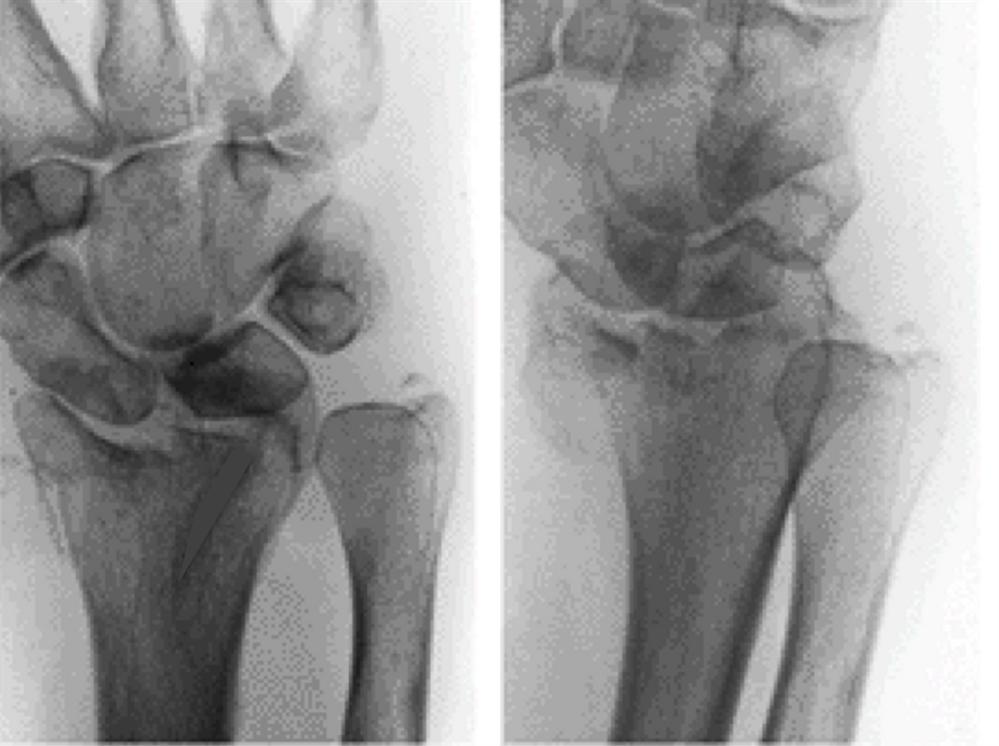

Diagnosis is made clinically and radiographically with orthogonal radiographs of. Distal radius fractures are the most common orthopaedic injury and generally result from fall on an outstretched hand. Hand most commonly displaced in the dorsal direction. Visible deformity of the wrist is usually noted.

A male patient, 44 years old, sustained intraarticular fracture of Die Punch Distal Radius Fracture Visible deformity of the wrist is usually noted. Diagnosis is made clinically and radiographically with orthogonal radiographs of. Distal radius fractures are the most common orthopaedic injury and generally result from fall on an outstretched hand. Hand most commonly displaced in the dorsal direction. Die Punch Distal Radius Fracture.